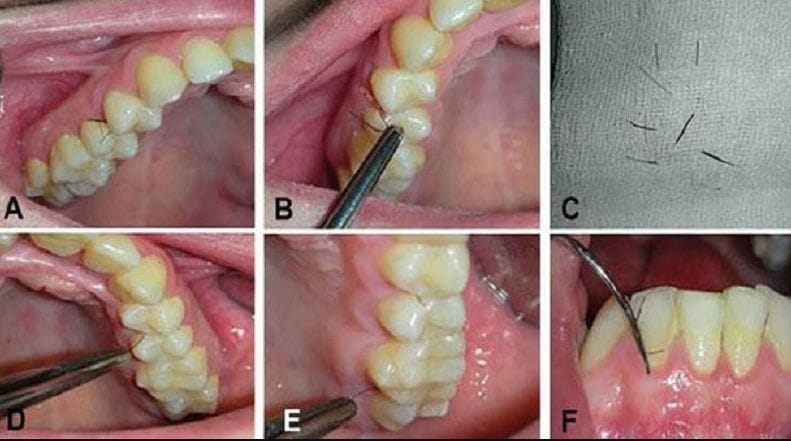

দাঁতের ফাঁকে মাড়ির ভিতর থেকে বেরিয়ে এসেছে লোম। এমনই বিরল এক রোগে আক্রান্ত ২৫ বছরের ইটালির তরুণী। তার এই অদ্ভুত রোগ অবাক করেছে চিকিৎসকদেরও। বছর দশেক আগে প্রথমবার তরুণী টের পান তার মুখের ভিতরে লোম গজাচ্ছে। পরীক্ষা করে দেখা যায়, তার শরীরে টেস্টোস্টেরনের মাত্রা অস্বাভাবিকভাবে বেশি। সেই সঙ্গে তার ডিম্বাশয়ে রয়েছে একাধিক সিস্ট।

মাড়ির লোম অনুবিক্ষণ যন্ত্রের নিচে রাখতেই আঁতকে ওঠেন চিকিৎসকরা। এবারের গজিয়ে ওঠা চুলের সংখ্যা এবং ধরন আগের চেয়ে একেবারে অন্যরকম। কীভাবে এমনটা হল, বুঝে উঠতে পারেন না চিকিৎসকরাও। নতুন করে শুরু হয় তার চিকিৎসা। বর্তমানে ইটালির ক্যাম্পানিয়া লুইগি ভানভিতেল্লিতে বিশ্ববিদ্যালয়ে চিকিৎসাধীন ওই তরুণী। তবে এখনও তিনি সম্পূর্ণভাবে রোগমুক্ত হয়েছেন কি না, তা জানা যায়নি। কিন্তু তরুণীর এমন রোগের কথা শুনে চমকে গিয়েছে গোটা বিশ্ব। এ ধরনের রোগীকে কীভাবে রোগমুক্ত করা যায়, তার জন্য নানা গবেষণা চলছে।